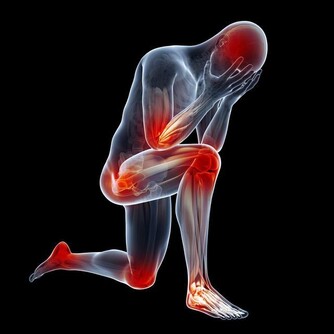

痛風,幾乎也是讓大家聞之色變的一類疾病了,因為一旦患上了痛風,不僅身體會長時間受到折磨,精神上也會感到十分痛苦,而且在痛風患者的日常生活中,稍有不慎就可能會導致其他病症一齊發作。